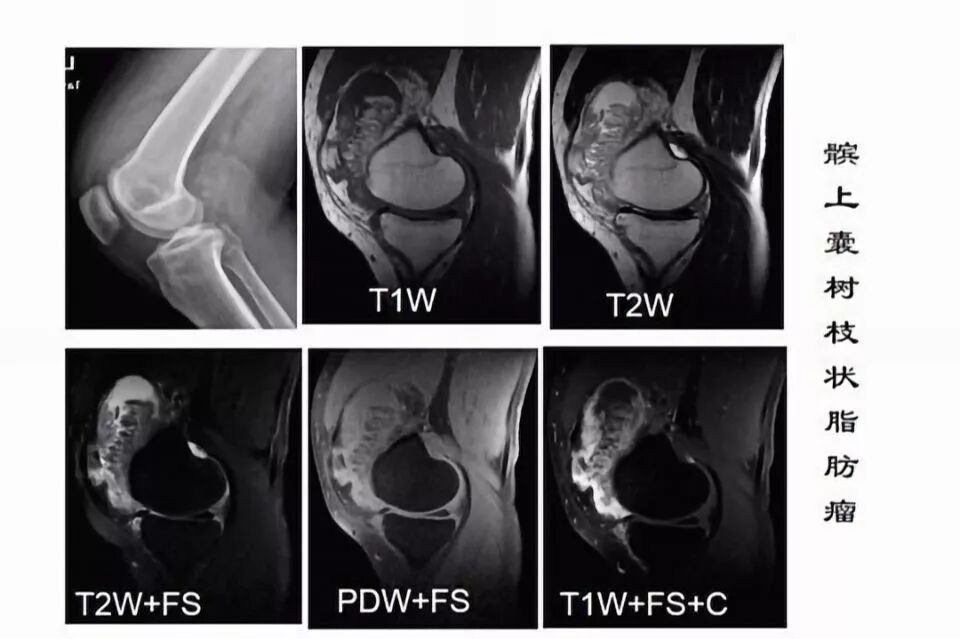

滑囊是关节囊外的囊性结构,可与关节囊相通,其作用是减少肌腱、骨和皮肤之间的摩擦。可以分为先天性滑囊和获得性滑囊。